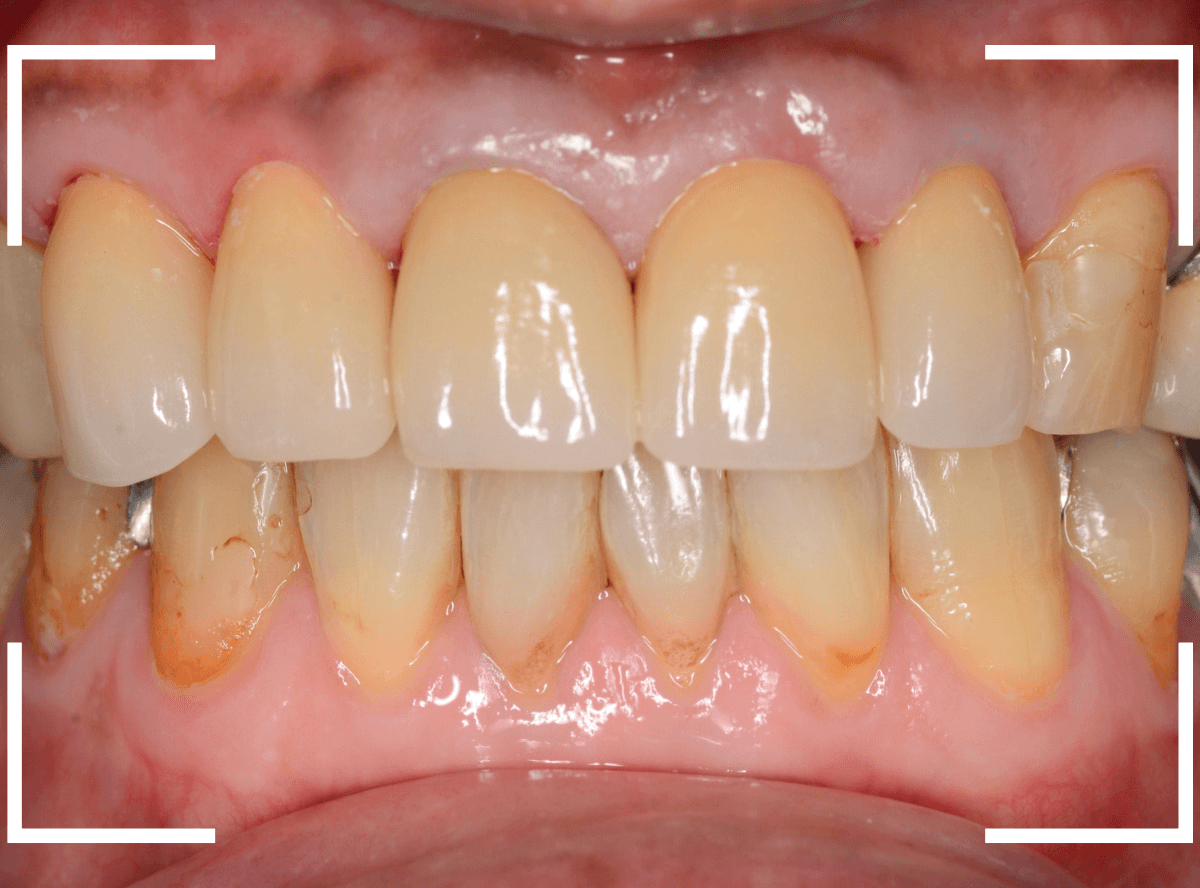

Case.16 保険のさし歯(レジン前装冠)をジルコニア・セラミックへ

以前に治療した上のさし歯を綺麗にやり直したいというご相談の患者さんです。

保険診療で行うさし歯「レジン前装冠」が入っています。

「レジン前装冠」は裏から撮影した写真を見ていただければわかるように、銀歯の上にレジン(プラスチック)を盛ったさし歯で、実質的には銀歯です。

銀歯の上にプラスチックを盛るために、歯をかなり大きく削る必要があったり、短期間で劣化・変色する(この方の差し歯も劣化してのっぺりした黄土色になっています)、金属の色素が歯肉に溶け出して歯肉が黒くなる(メタル・タトゥー)などのデメリットがあります。